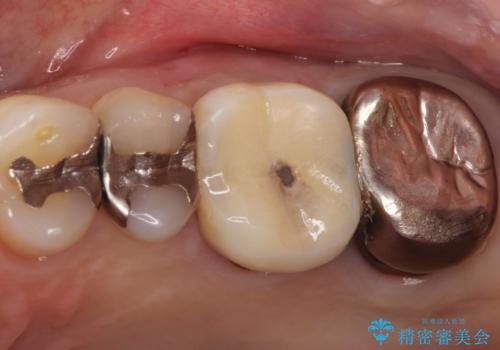

【再根管治療】オールセラミッククラウンによる修復

- 治療途中の歯があることを主訴に来院されました。

根管治療を行なったのちオールセラミックにて修復治療を行なっております。

第二大臼歯の治療は希望されませんでした。